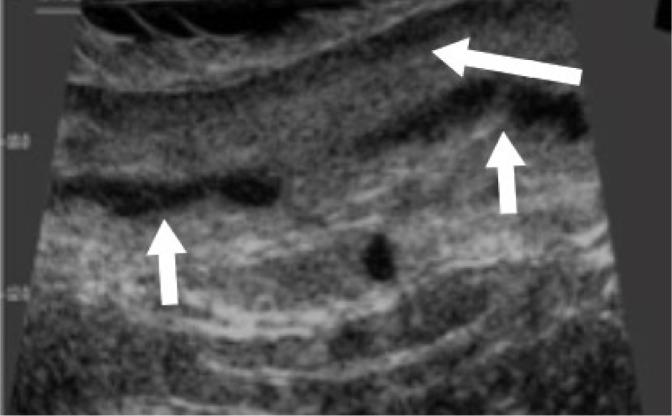

Paget's disease of the vulva is a rare skin cancer accounting for less than 1% of all vulvar neoplasias. Surgery is the first treatment of choice. Unfortunately, it is insufficient in many cases, which require further treatment, and the risk of recurrence is high. We present a case of an 85-year-old woman who underwent surgery due to Paget's disease of the vulva. A preoperative skin imaging using a high-frequency 48 MHz mechanical probe was used to assess the lesion margins. Typical high-frequency ultrasonographic features of vulvar Paget's disease were identified and analyzed. This is the first report of high-frequency ultrasonography imaging of vulvar Paget's disease.

外阴佩吉特病是一种罕见的皮肤癌,占所有外阴肿瘤的比例不到1%。手术是首选的治疗方法。不幸的是,在许多情况下手术并不充分,需要进一步治疗,且复发风险很高。我们报告一例85岁因外阴佩吉特病接受手术的女性病例。术前使用高频48MHz机械探头进行皮肤成像以评估病变边缘。识别并分析了外阴佩吉特病典型的高频超声特征。这是外阴佩吉特病高频超声成像的首例报告。